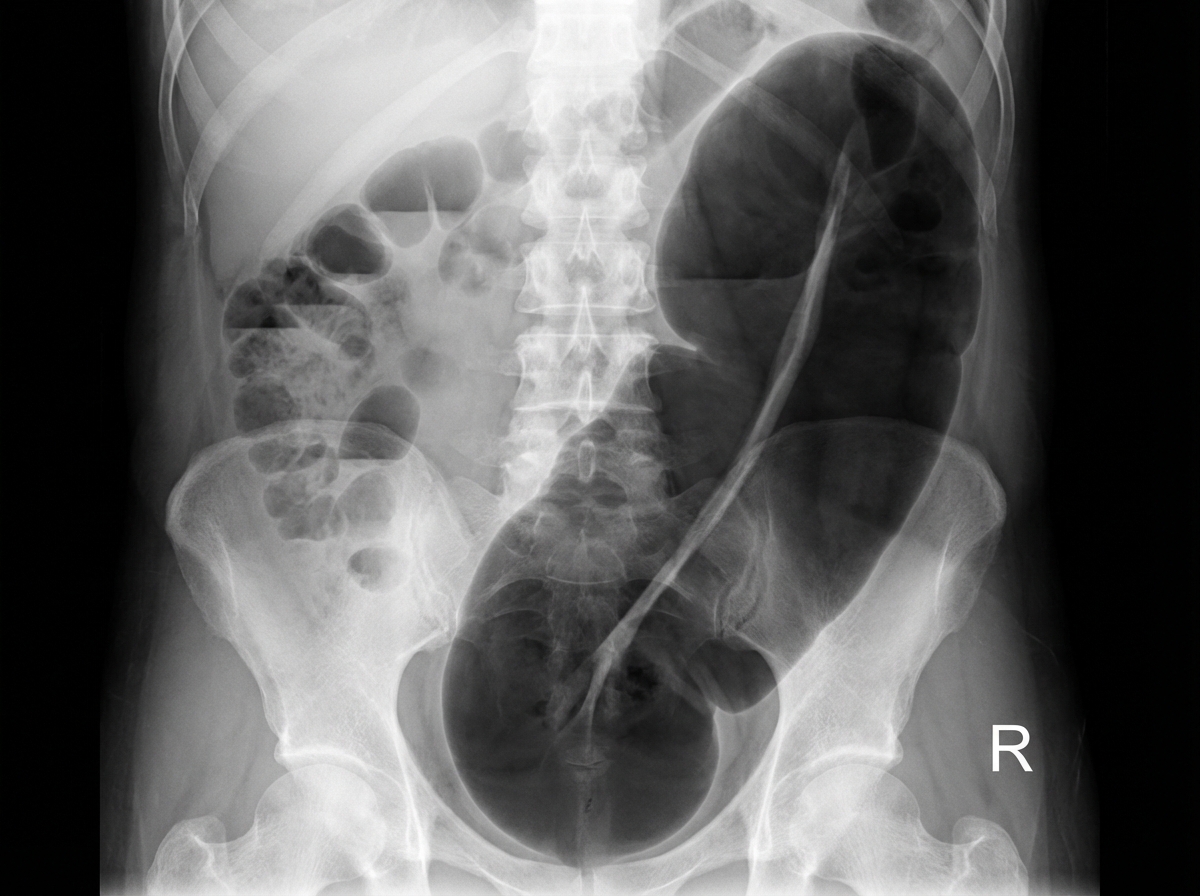

An X-ray of the abdomen reveals a specific finding. Identify the finding and its associated pathology:

Explanation: ***Coffee bean sign - Sigmoid volvulus*** - The **coffee bean sign** on plain abdominal X-ray is **pathognomonic** for sigmoid volvulus, showing a characteristic dilated sigmoid loop resembling a coffee bean. - This finding represents **twisted sigmoid colon** with air-fluid levels, typically seen in the **left upper quadrant** extending toward the right side. *Bird beak sign - Achalasia* - The **bird beak sign** is seen on **barium swallow studies**, not plain abdominal X-rays, showing narrowed gastroesophageal junction. - This finding is specific to **achalasia** involving the **esophagus**, not intestinal pathology visible on abdominal radiographs. *Coffee bean sign - Cecal volvulus* - **Cecal volvulus** typically presents with a **dilated cecum** in the left upper quadrant, but lacks the characteristic coffee bean configuration. - The radiographic appearance is more of a **kidney-shaped** or **comma-shaped** dilated bowel loop rather than the coffee bean sign. *Bird of prey sign - Sigmoid volvulus* - The **bird of prey sign** is a **barium enema** finding, not visible on plain abdominal X-rays. - This sign shows the **twisted point** of sigmoid volvulus on contrast studies, appearing like a bird's beak, but requires contrast enhancement to visualize.